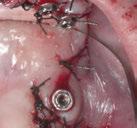

Se obtuvieron modelos de estudio (Figuras 3-6) digitales mediante un escáner confocal de luz azul estructurada (PrimeScan, Dentsply Sirona) y se planificó un protocolo de desgaste mínimamente necesario y conservador de las estructuras

Figura 1. Caso inicial. Figura 2. Vista oclusal superior.

dentarias, cumpliendo parámetros biológicos, terapéuticos, mecánicos y estéticos. Después se realizó un modelado digital retrospectivo (Figuras 7-11) para generar modelos impresos 3D para realizar el mock up funcional, estético y como guía para las preparaciones (Figuras 12-15). Con ello, se efectuaron las preparaciones dentarias y los registros intermaxilares y, posteriormente, se digitalizaron ambos maxilares (Figuras 16-21)

En las piezas 16 y 17 el paciente presentaba restauraciones atornilladas de metalcerámica sobre implantes oseointegrados. Se planificó realizar estas en una fase posterior a la rehabilitación de las piezas dentarias mediante flujo digital con bases de titanio y cuerpos de escaneo.